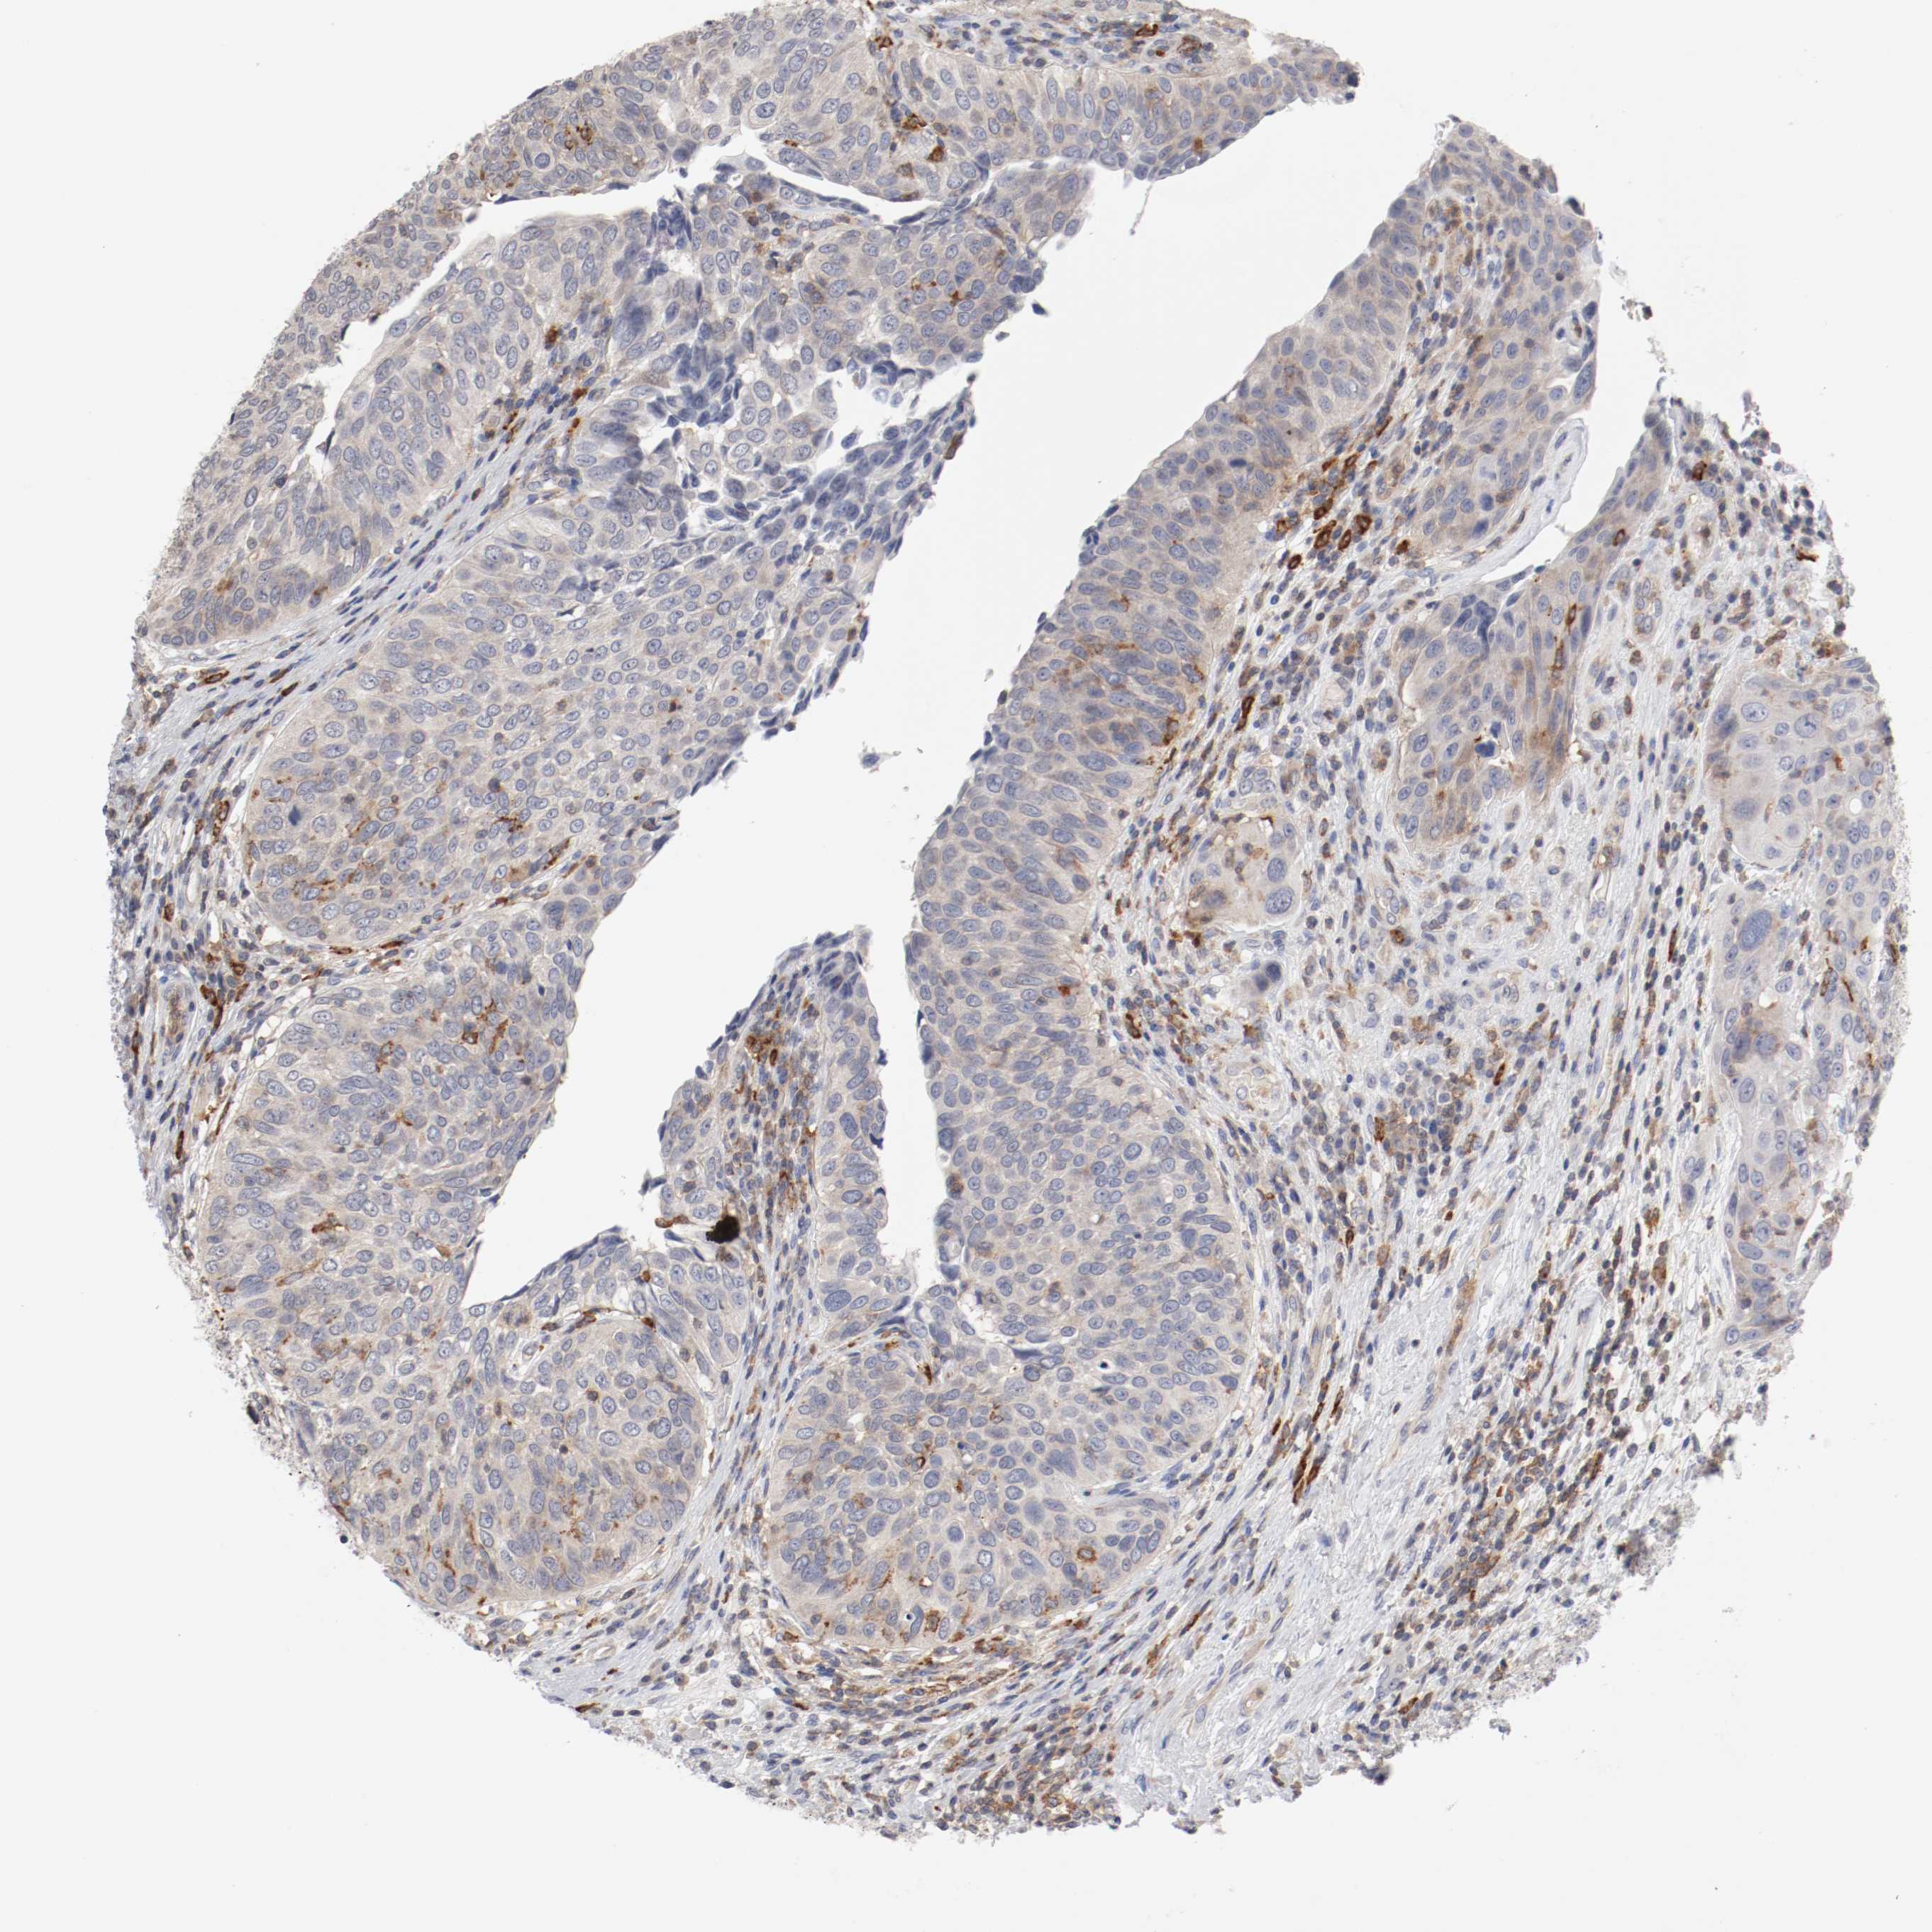

UROTHELIAL CANCER - Protein expressioni

A mouse-over function shows sample information and annotation data. Click on an image to view it in a full screen mode. Samples can be filtered based on level of antibody staining by selecting one or several of the following categories: high, medium, low and not detected. The assay and annotation is described here.

Note that samples used for immunohistochemistry by the Human Protein Atlas do not correspond to samples in the TCGA dataset.

Antibody stainingi

Antibody staining in the annotated cell types in the current human tissue is reported as not detected, low, medium, or high, based on conventional immunohistochemistry profiling in selected tissues. This score is based on the combination of the staining intensity and fraction of stained cells.

Each image is clickable and will lead to virtual microscopy that enables deeper exploration of all samples and also displays staining intensity scores, fraction scores and subcellular localization as well as patient and tissue information for each sample.

Antibody HPA027956

Antibody CAB004350

Urothelial carcinoma, Low grade

Urothelial carcinoma, High grade